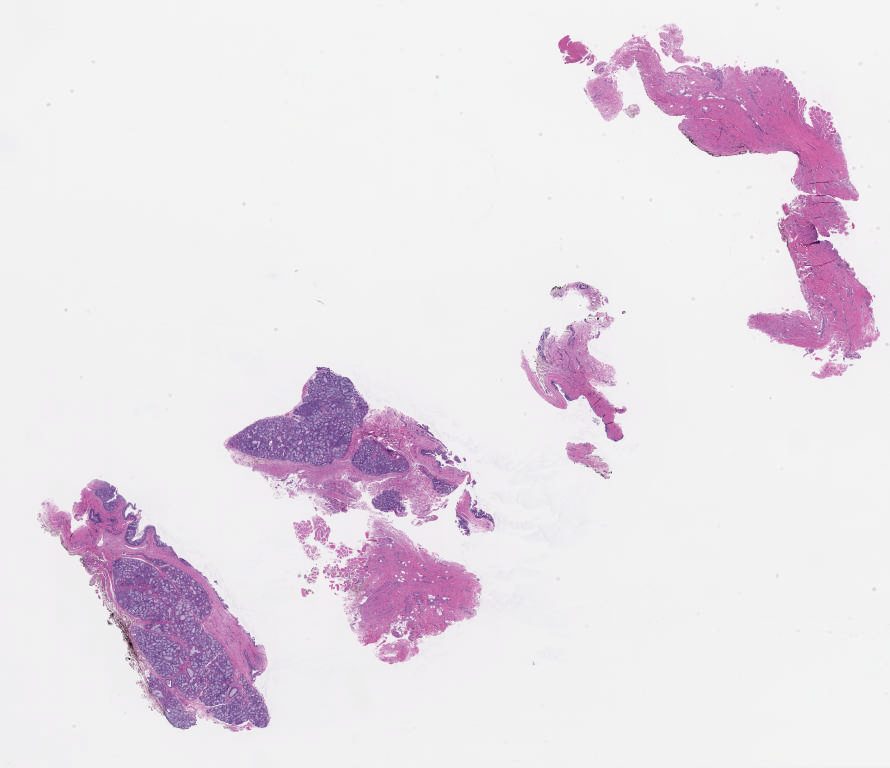

University of Pittsburgh Oral Pathology Study Set Summer 2025\Case02

1800691.svs